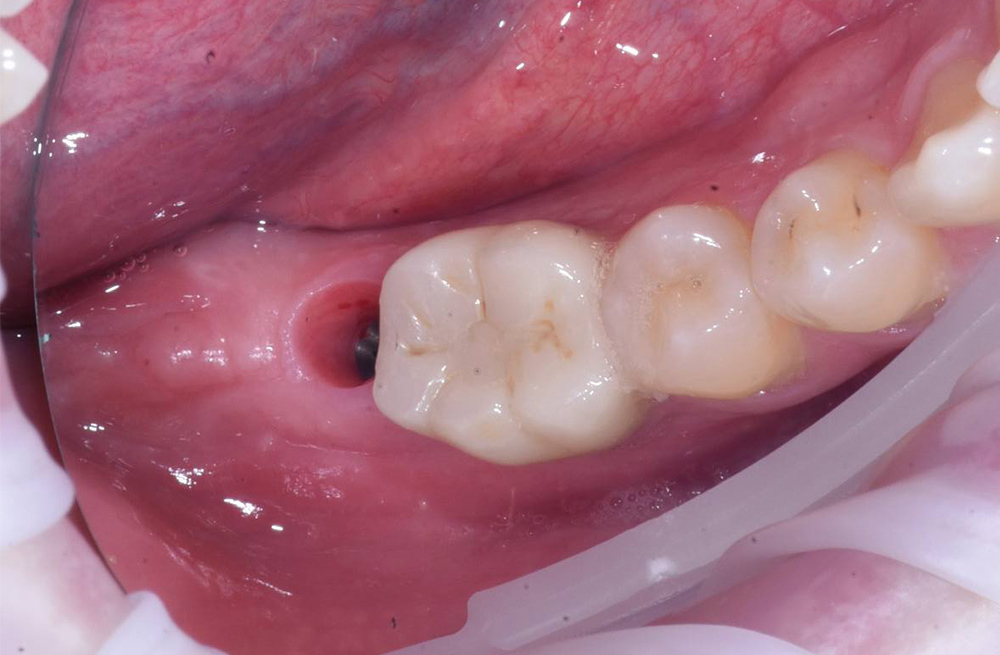

Замещение отсутствующего жевательного зуба имплантом Straumann и циркониевой реставрацией